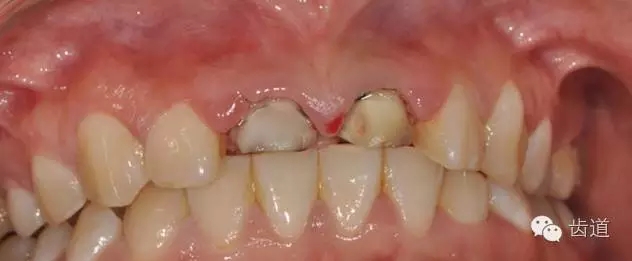

舌側(cè)觀,基牙咬合緊,間隙小,原烤瓷冠為金屬舌面

11、21拆除原烤瓷冠,可見(jiàn)基牙唇側(cè)牙體預(yù)備量過(guò)大,肩臺(tái)位于齦下2--3mm,腐質(zhì)較多。